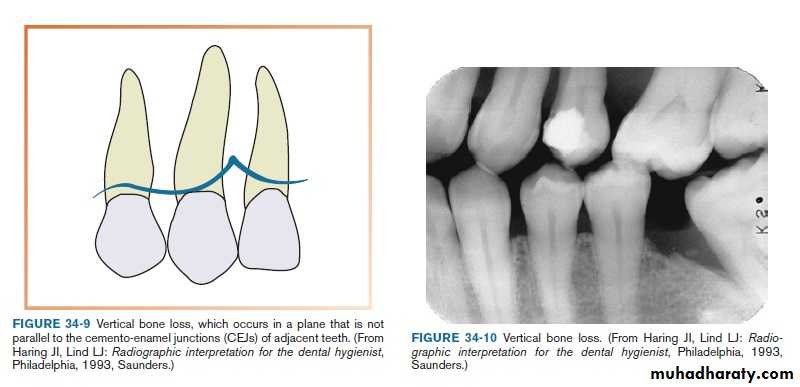

vertical (angular) bone loss:

Bone loss doesn’t occur in plane parallel to CEJs of adjacent teeth.Vertical bone loss

Vertical bone defects-are also called proximal intrabony defects. The defect extends apically2- Distribution